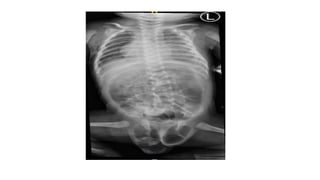

Foto Baby Gram RSWS 14-7-2022

• Kesan:

- Pneumonia Sinistra

- Multiple bayangan lusen berkantung dengan loop loop usus pada

cavum scrotalis suspek hernia scrotalis bilateral

- Dilatasi loop loop usus

Foto Baby GramRSWS 14-7-2022 • Kesan: - Pneumonia Sinistra - Multiple bayangan lusen berkantung dengan loop loop usus pada cavum scrotalis suspek hernia scrotalis bilateral - Dilatasi loop loop usus